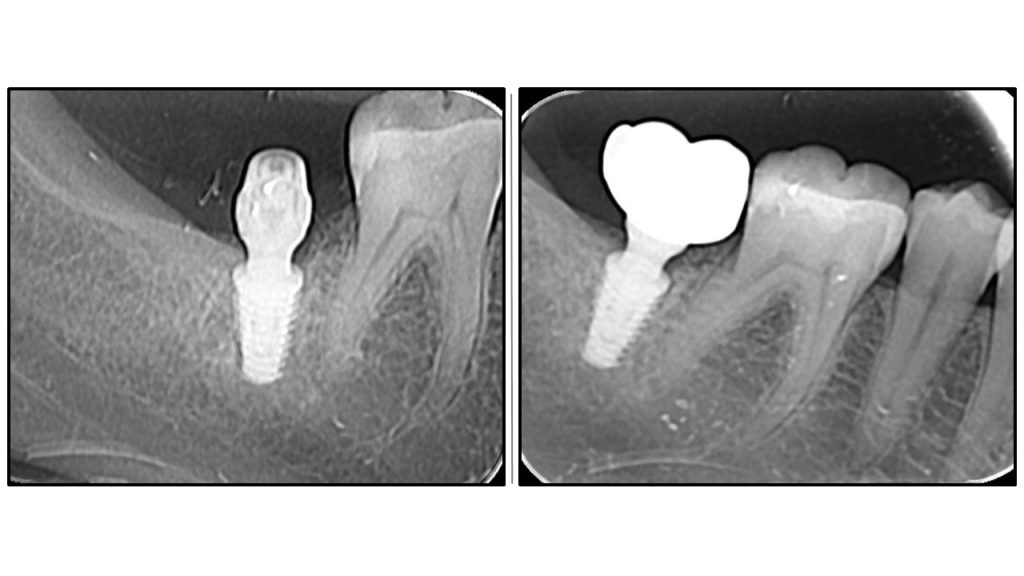

Bicortical stability achieved by the abutment.

Bicortical stability by apical engagement of the compact sinus floor and crestal bone by an abutment